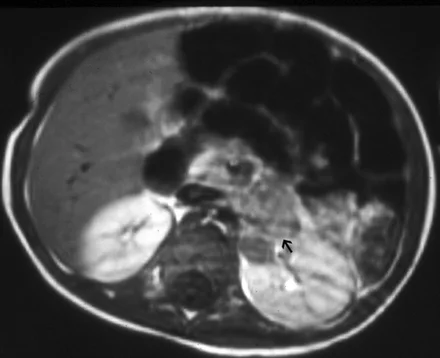

Rhabdomyosarcoma = Embryonal Sarcoma

- Most common primary solid orbital malignancy of childhood

- Average age at presentation 7-8 years

- Sudden onset and rapid evolution of unilateral proptosis

- 90% 5 years survival rate with timely and appropriate treatment